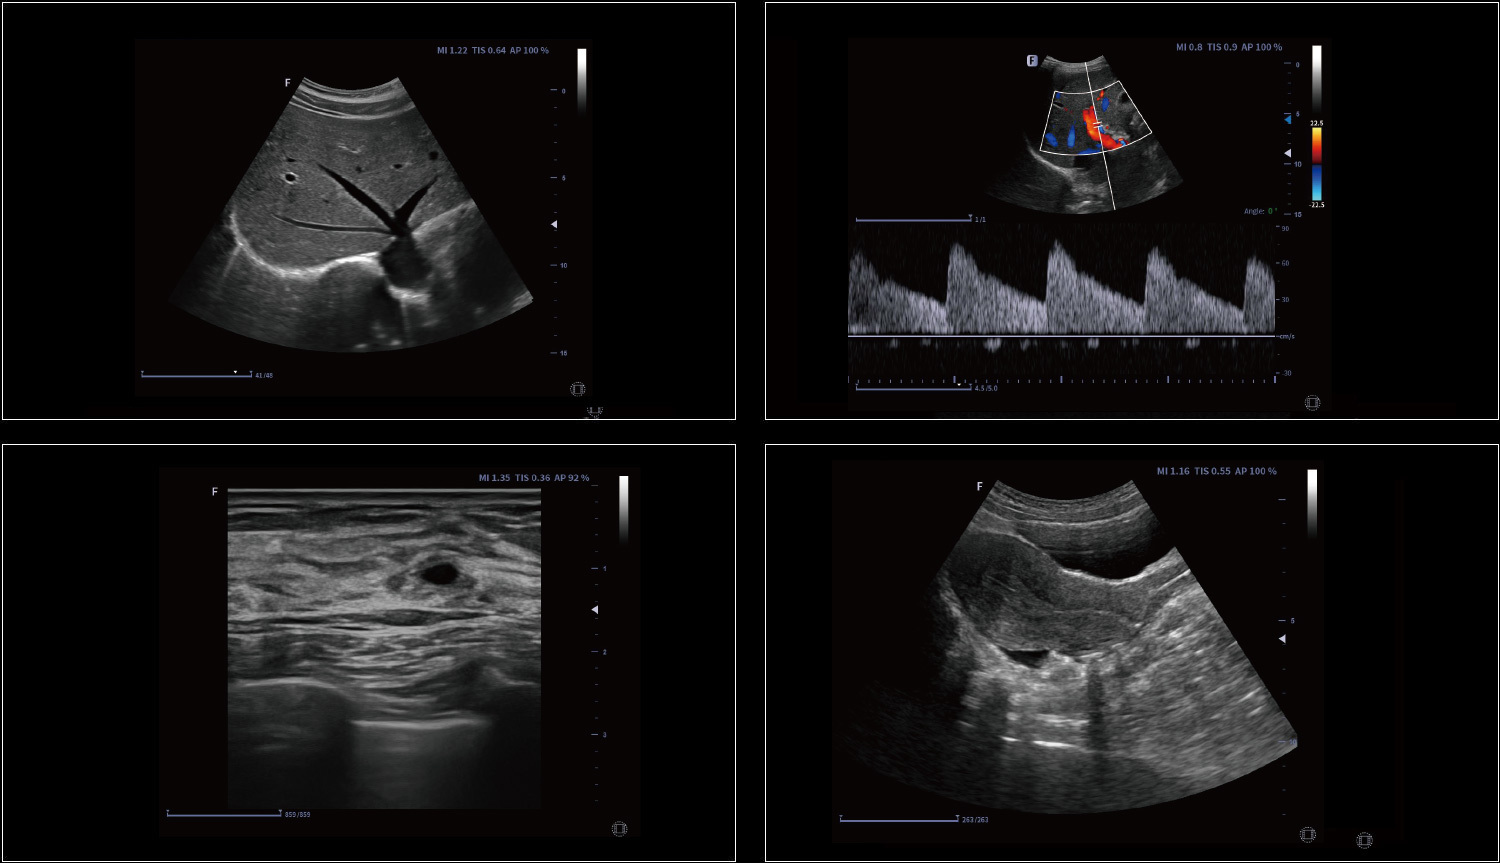

Rozszerzone pole widzenia wyświetla więcej informacji obrazowych bez utraty jakości obrazu. Jest wygodnym podejściem do dużych organów, zwłaszcza struktur układu mięśniowo-szkieletowego. Posiada wskazania dotyczące kierunku i prędkości skanowania.

Elastografia w czasie rzeczywistym to nowa nieinwazyjna i bezbolesna technika, która pomaga określić twardość organów oraz innych struktur takich jak piersi czy tarczyca. Obrazowanie elastyczne dostarcza użytkownikom dynamicznych informacji wizualnych i pokazuje sztywność organów, co jest pomocne w bezpośredniej i ilościowej diagnozie oraz leczeniu.

Providing tutorial information regarding to abdomen, vascular, small parts, GYN, MSK, etc., including standard ultrasound image, anatomical diagram, scanning technique and tips.